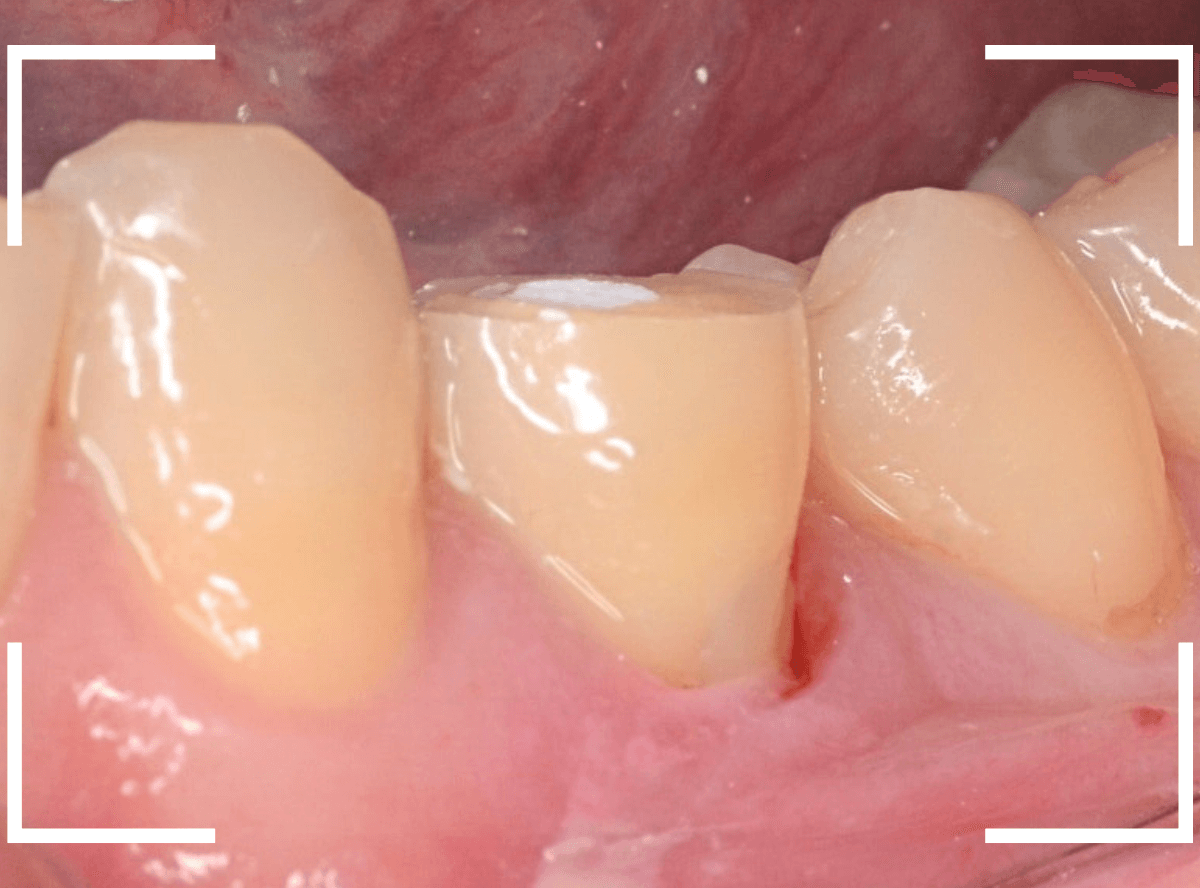

実際の治療例 神経をとらなければいけないほど、大きな虫歯がわからない

「歯がとても痛む」という患者さんが来院されました。

初見では、特に大きな虫歯や歯周病という感じではありませんでした。

しかし、ピンセットで歯を叩くと、確実にこの歯で反応があります。

レントゲン写真でも、大きな虫歯などはなさそうな感じです。

もう一度歯を確認すると、つけ根がうっすらと虫歯っぽいです。

これかな?しかし、風をかけてもしみません。

うーん。。。

レントゲン写真ももう一度確認してみます。

もしかすると、歯肉の中で虫歯が広がってるのかもしれません。

側面からの虫歯ですので、どれくらい虫歯が深いのかはこの写真からはわかりません。

患者さんに状況をお話しし、麻酔をして慎重に歯を削って調べてみると、神経まで達する虫歯でした(><)

これが痛みの原因で間違いなさそうです。

しみるなどの症状が出る事なく、歯の側面が神経まで達する虫歯になる事は珍しいです。

虫歯と神経を除去し、蓋をして何回か、神経の治療が続く旨ご説明し、今日は治療終了です。

今回は、明確な痛みがあったためにまだ診断がつきやすかったですが、そうでない事もあります。

虫歯の診断も奥が深いです。